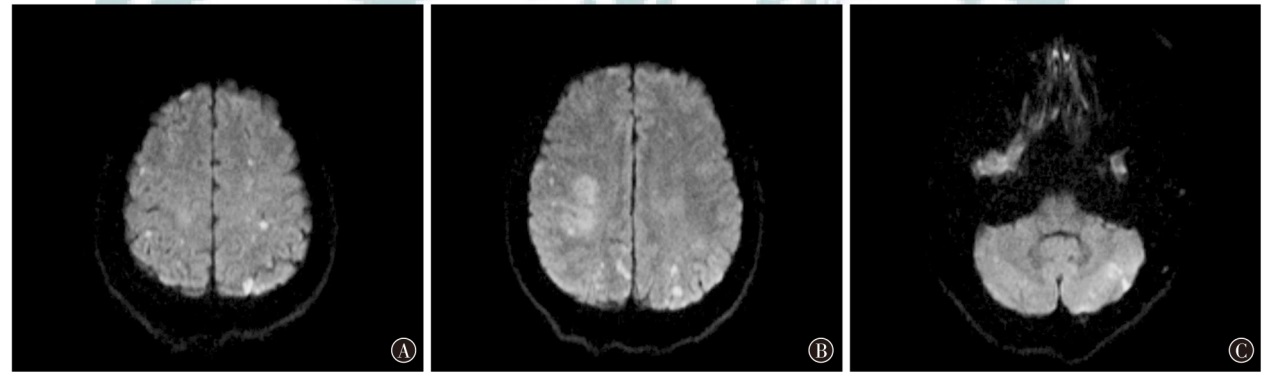

Ling Y, Li Y, Zhang X, et al. Clinical features of trousseau's syndrome with multiple acute ischemic strokes[J]. Neurol Sci, 2022, 43(4): 2405-2411. DOI: 10.1007/s10072-021-05619-y.